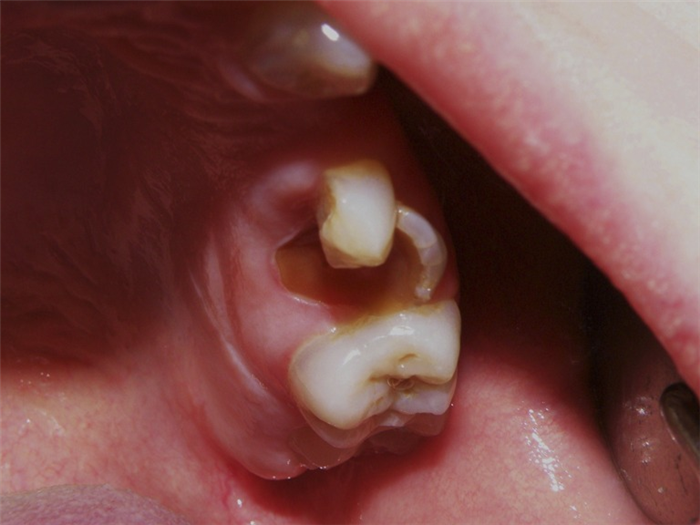

Уже в младшем школьном возрасте коронки постоянных зубов начали скалываться от физиологической нагрузки, в первую очередь шестые зубы. Границы сколов проходили по глубоким слоям дентина (рис. 2).

Рис. 2. Глубокие сколы зубов.

У обеих сестер более интенсивно окрашены зубы нижней челюсти. У старшей сестры зубы более крупные и имеют бочкообразную форму, у младшей бочкообразность зубов менее выраженна. Все зубы устойчивы. Имеются множественные сколы зубов. Края сколов находятся под десной, а линии сколов проходят по предполагаемым границам полостей зубов. Полости зубов облитерированы. Все участки обнаженного дентина имеют коричневый цвет, тверды и безболезненны при зондировании (рис. 3).

Рис. 3. Цвет обнаженного дентина.

Холодовая проба отрицательная. Визуально заметная стертость окклюзионных поверхностей наблюдается только в области нижних резцов младшей сестры. Кариесом поражен только один зуб у старшей сестры. При рентгенологическом исследовании сразу же обращает на себя внимание полная облитерация полостей зубов (рис. 4).